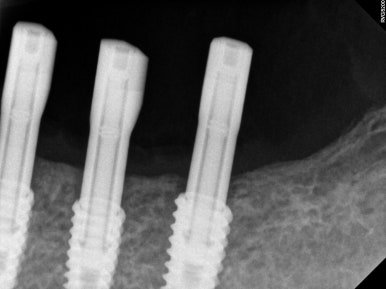

임플란트를 잇몸 안에 모두 묻어놓았기 때문에 (submerged) 추후에 임프란트 보철물을 연결할 수 있도록 치유지대주 (healing abutment)를 연결해주어야 합니다.

이 간단한 시술을 임플란트 2차 수술이라고 부릅니다.

임플란트 2차 수술을 얘기하면, 대부분의 환자분들이 또 수술을 해야하냐고 싫어하시지만... 임플란트 2차 수술은 학술적으로 보았을 때, 단순히 뚜껑을 하나 바꿔껴내는 행위는 아닙니다.

추후 제작될 임플란트 보철물 주변의 잇몸의 성상을 조성할 수 있고, 경우에 따라 잇몸이식술도 시행하여 보다 관리가 용이한 환경을 만들어내는 소수술이라고 보시는게 맞습니다.

아래턱 어금니 임플란트에 임플란트 2차 수술을 시행하고나서 약 10일 뒤 실밥을 제거합니다.